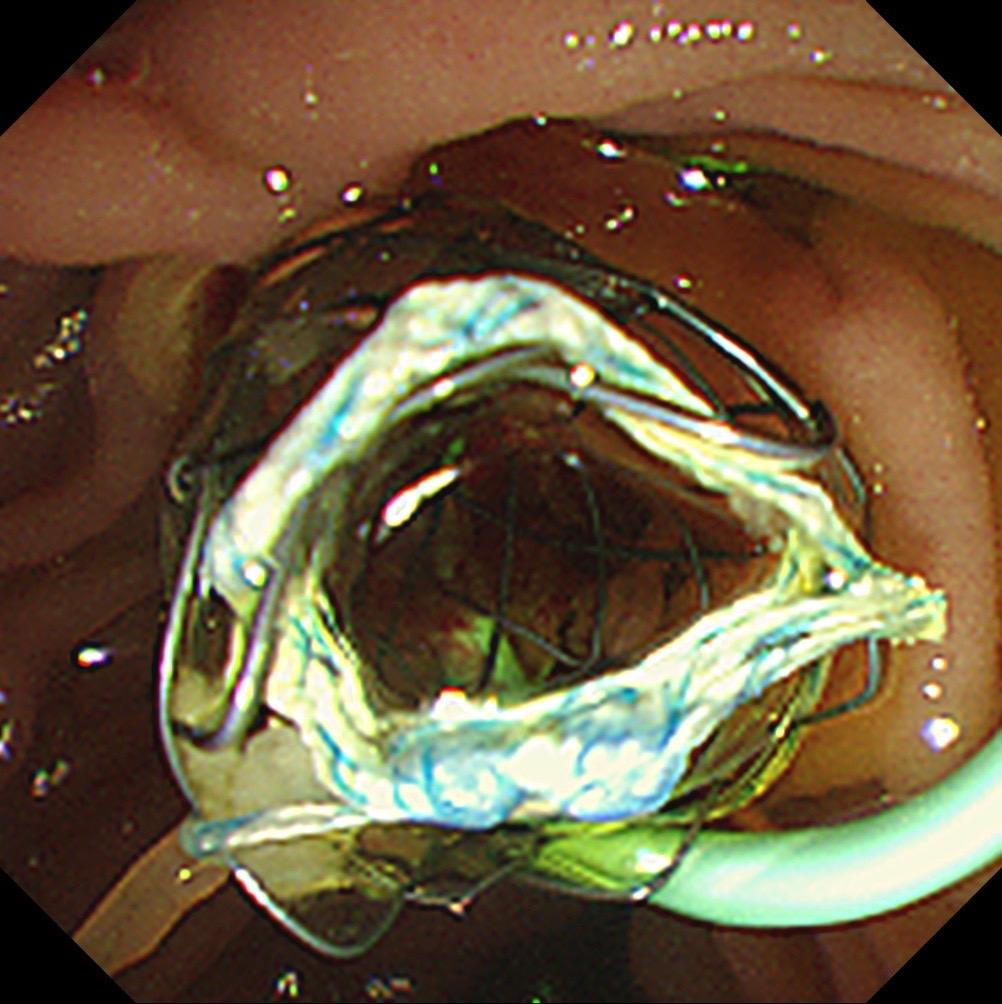

内镜医生最有成就感的事?发现早癌!这个月做了三十台四级手术,一些疑难杂症也是费力老鼻子劲了,但这些和发现早癌相比微不足道!看一个医院胃肠镜的水平,最重要的一个指标是早癌发现率!